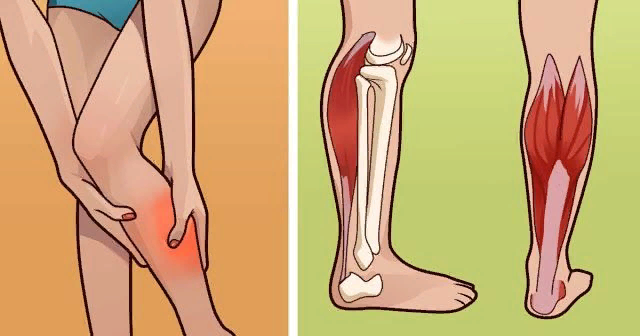

Диабет и судороги ног. Всем привет.Статья о рационе про рацион против судорог ног. Причина судорог мышц, которые очень часто бывают при диабете-это недостаток